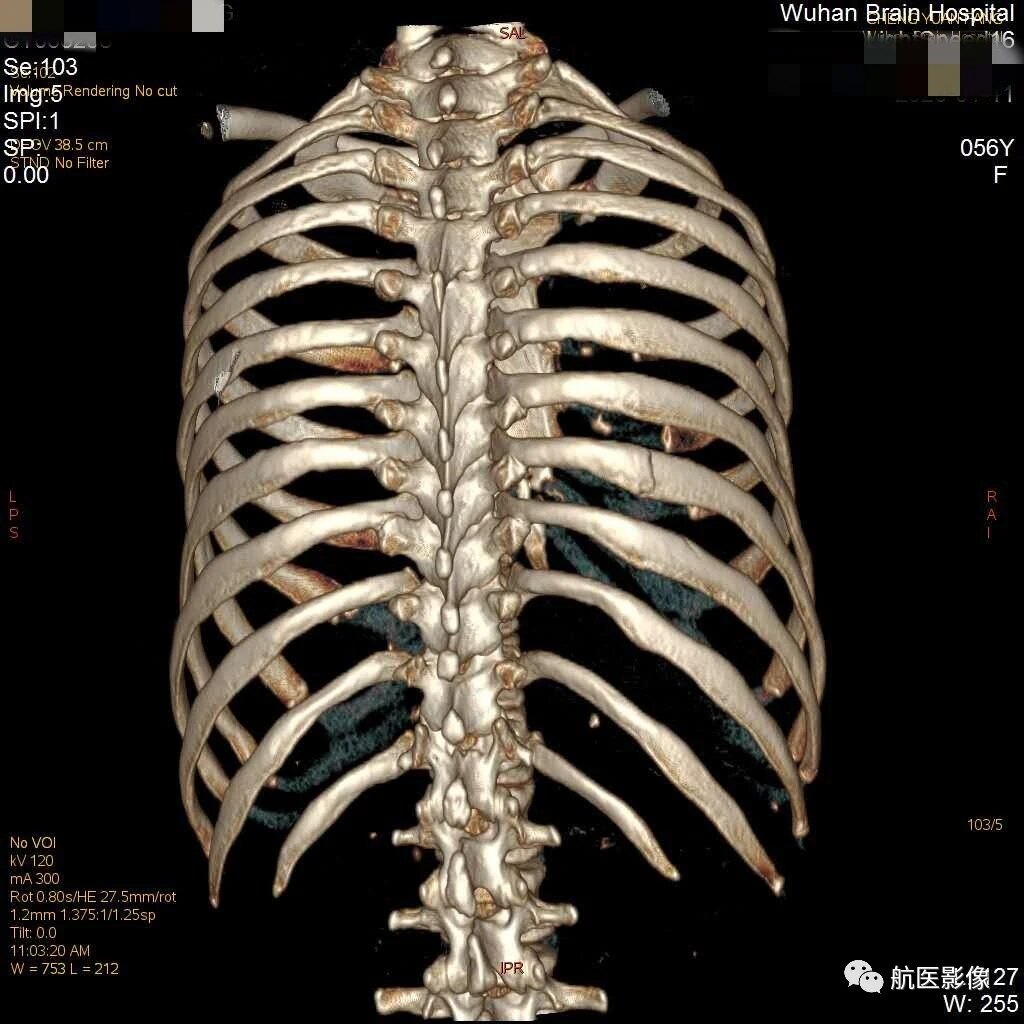

1 什麼是肋骨?肋骨共 12 對,左右對稱分佈在胸旁,與胸椎和胸骨連接形成胸廓,用來保護肺、心臟、肝臟等器官的骨骼,是整個胸腔的構架。2 肋骨骨折多發生在哪裡?肋骨的生理結構特點決定了最易折斷的部位,第 1—3 肋骨較短 胸部正位双侧肋骨未见明显错位骨折,主动脉硬化。 ct可见右侧第五前肋骨折。老年人,肺纹理粗乱,前肋靠近胸骨,重叠较多,易漏诊。 如何避免肋骨骨折的漏诊? 1询问患者有无受伤病史,车祸,摔伤,撞伤等。肋骨骨折 肋骨は左右12対の骨で背中の胸椎から前胸部の胸骨までかごのように胸腔を形成しており (図1)、その中に存在する心臓や肺ばかりでなく、腹腔内の肝臓、脾臓、腎臓の一部を保護しています。 ただ、11、12番目の肋骨の前方は胸骨にはくっついていません。 肋骨骨折は、胸部外傷の中で最も多くみられるものです。 その原因は机やタンスの角にぶつけたと

为什么肋骨骨折ct检查一定要做三维成像 肋骨骨折

肋骨骨折ct扫描三维成像少不得 Qtc Care